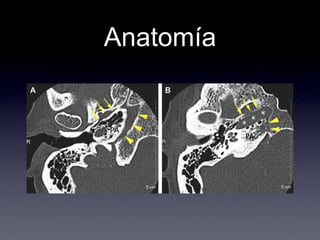

Anatomía.Localizado entre:oído interno hacia lateralfisura petro-occipital hacia medialfisura petro-esfenoidal hacia anterior.

Anatomía